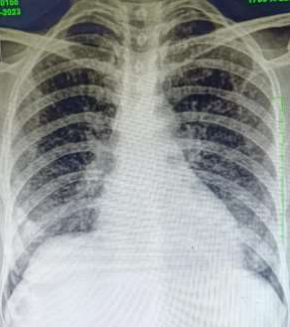

Figure 2- Chest X-ray & Computed tomography of thorax showing miliary nodules in lungs

Figure 2 (a), Figure 2 (b)

The endoscopy findings were consistent with presence of ulcer in fundic region (Figure 1) along with presence of well circumscribed circumferential soft,friable and fleshy lesion of approxiametely 1  cm. The bite on bite biopsies were taken from that area and send for analysis. The biopsy report was consistent with caseating granulomas with numerous acid-fast bacilli detected with Ziehl-Neelsen stain and  immunohistochemical analyis for Helicobacter pylori was negative. On subsequent evaluation patient was found to have multiple military nodules on chest X-ray (Figure 2a) and which was confirmed with computed tomography of thorax (Figure 2b).